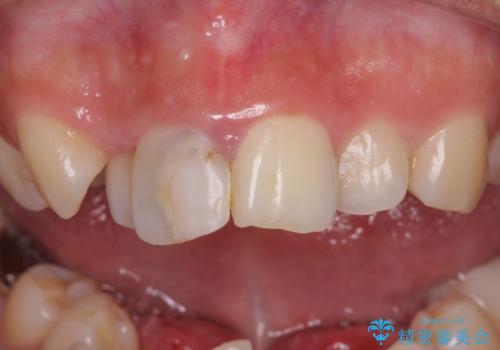

矯正治療を行う前に、根管治療の必要な上顎前歯と下顎大臼歯の根管治療を行い、矯正治療の途中で下顎の欠損部にインプラント埋入することとし、矯正治療後に補綴治療を行うこととしました。

- 天然歯を削ります

- 硬い素材は天然歯を傷つけてしまう場合があります

- かみ合わせや歯ぎしりが強すぎる方はセラミックが割れてしまう可能性があります